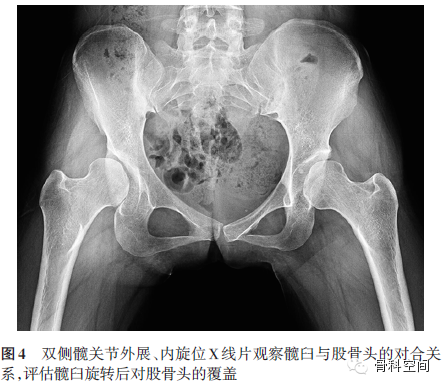

(三)髋关节功能位X线片[12](双侧髋关节外展、下肢内旋位片):观察功能位下髋臼与股骨头的对合关系(图4),是判断能否施行髋臼周围截骨术的不可或缺的检查项目。